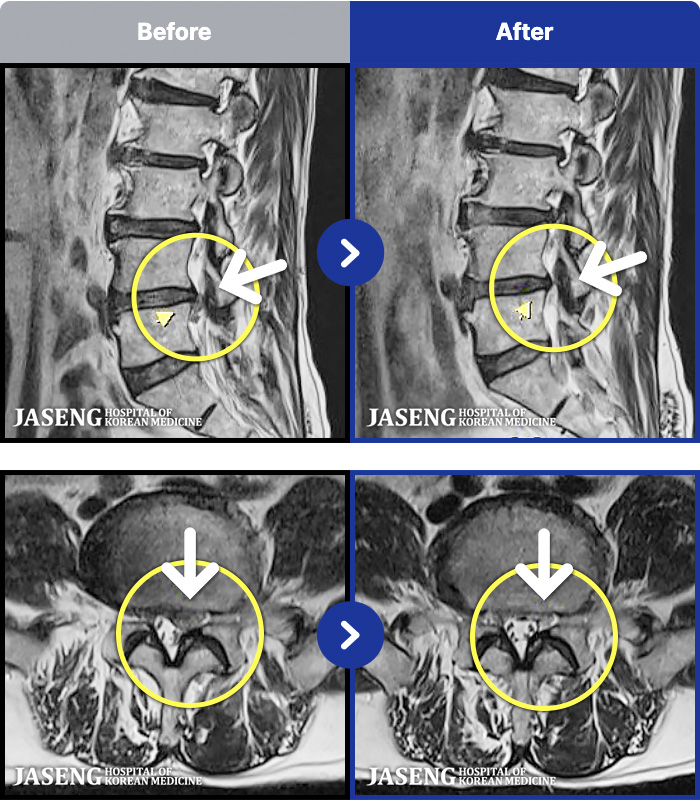

1,296 MRI ũ ʸ Ȯϼ.

ȯںп Ǹ ǿ ԿǾ, ο ġ ۿ Ƿ ġḦ Ͻñ ٶϴ.